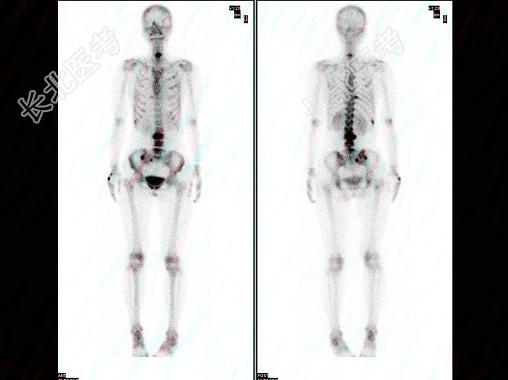

多项选择题女,28岁, 左乳癌术后1年,无明显不适, 行Tc-MDP骨显像如图,可能的诊断是 ( )

A、多发骨转移瘤

B、大致正常的影像

C、骨盆有溶骨性病变

D、有双轨征存在

E、下位颈椎转移瘤